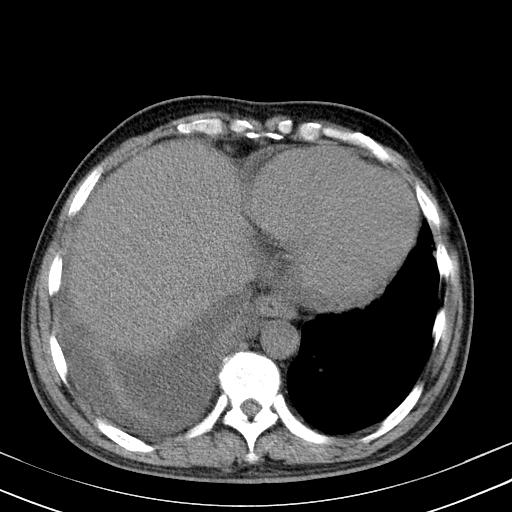

以下是引用zxl51642在2010-3-21 17:06:00的发言:[br]右下中心型肺癌并阻塞性肺炎/不张,纵膈淋巴结肿大,右侧大量胸腔积液,左侧少量胸腔积液,少量腹水。建议纤维支气管镜进一步检查。